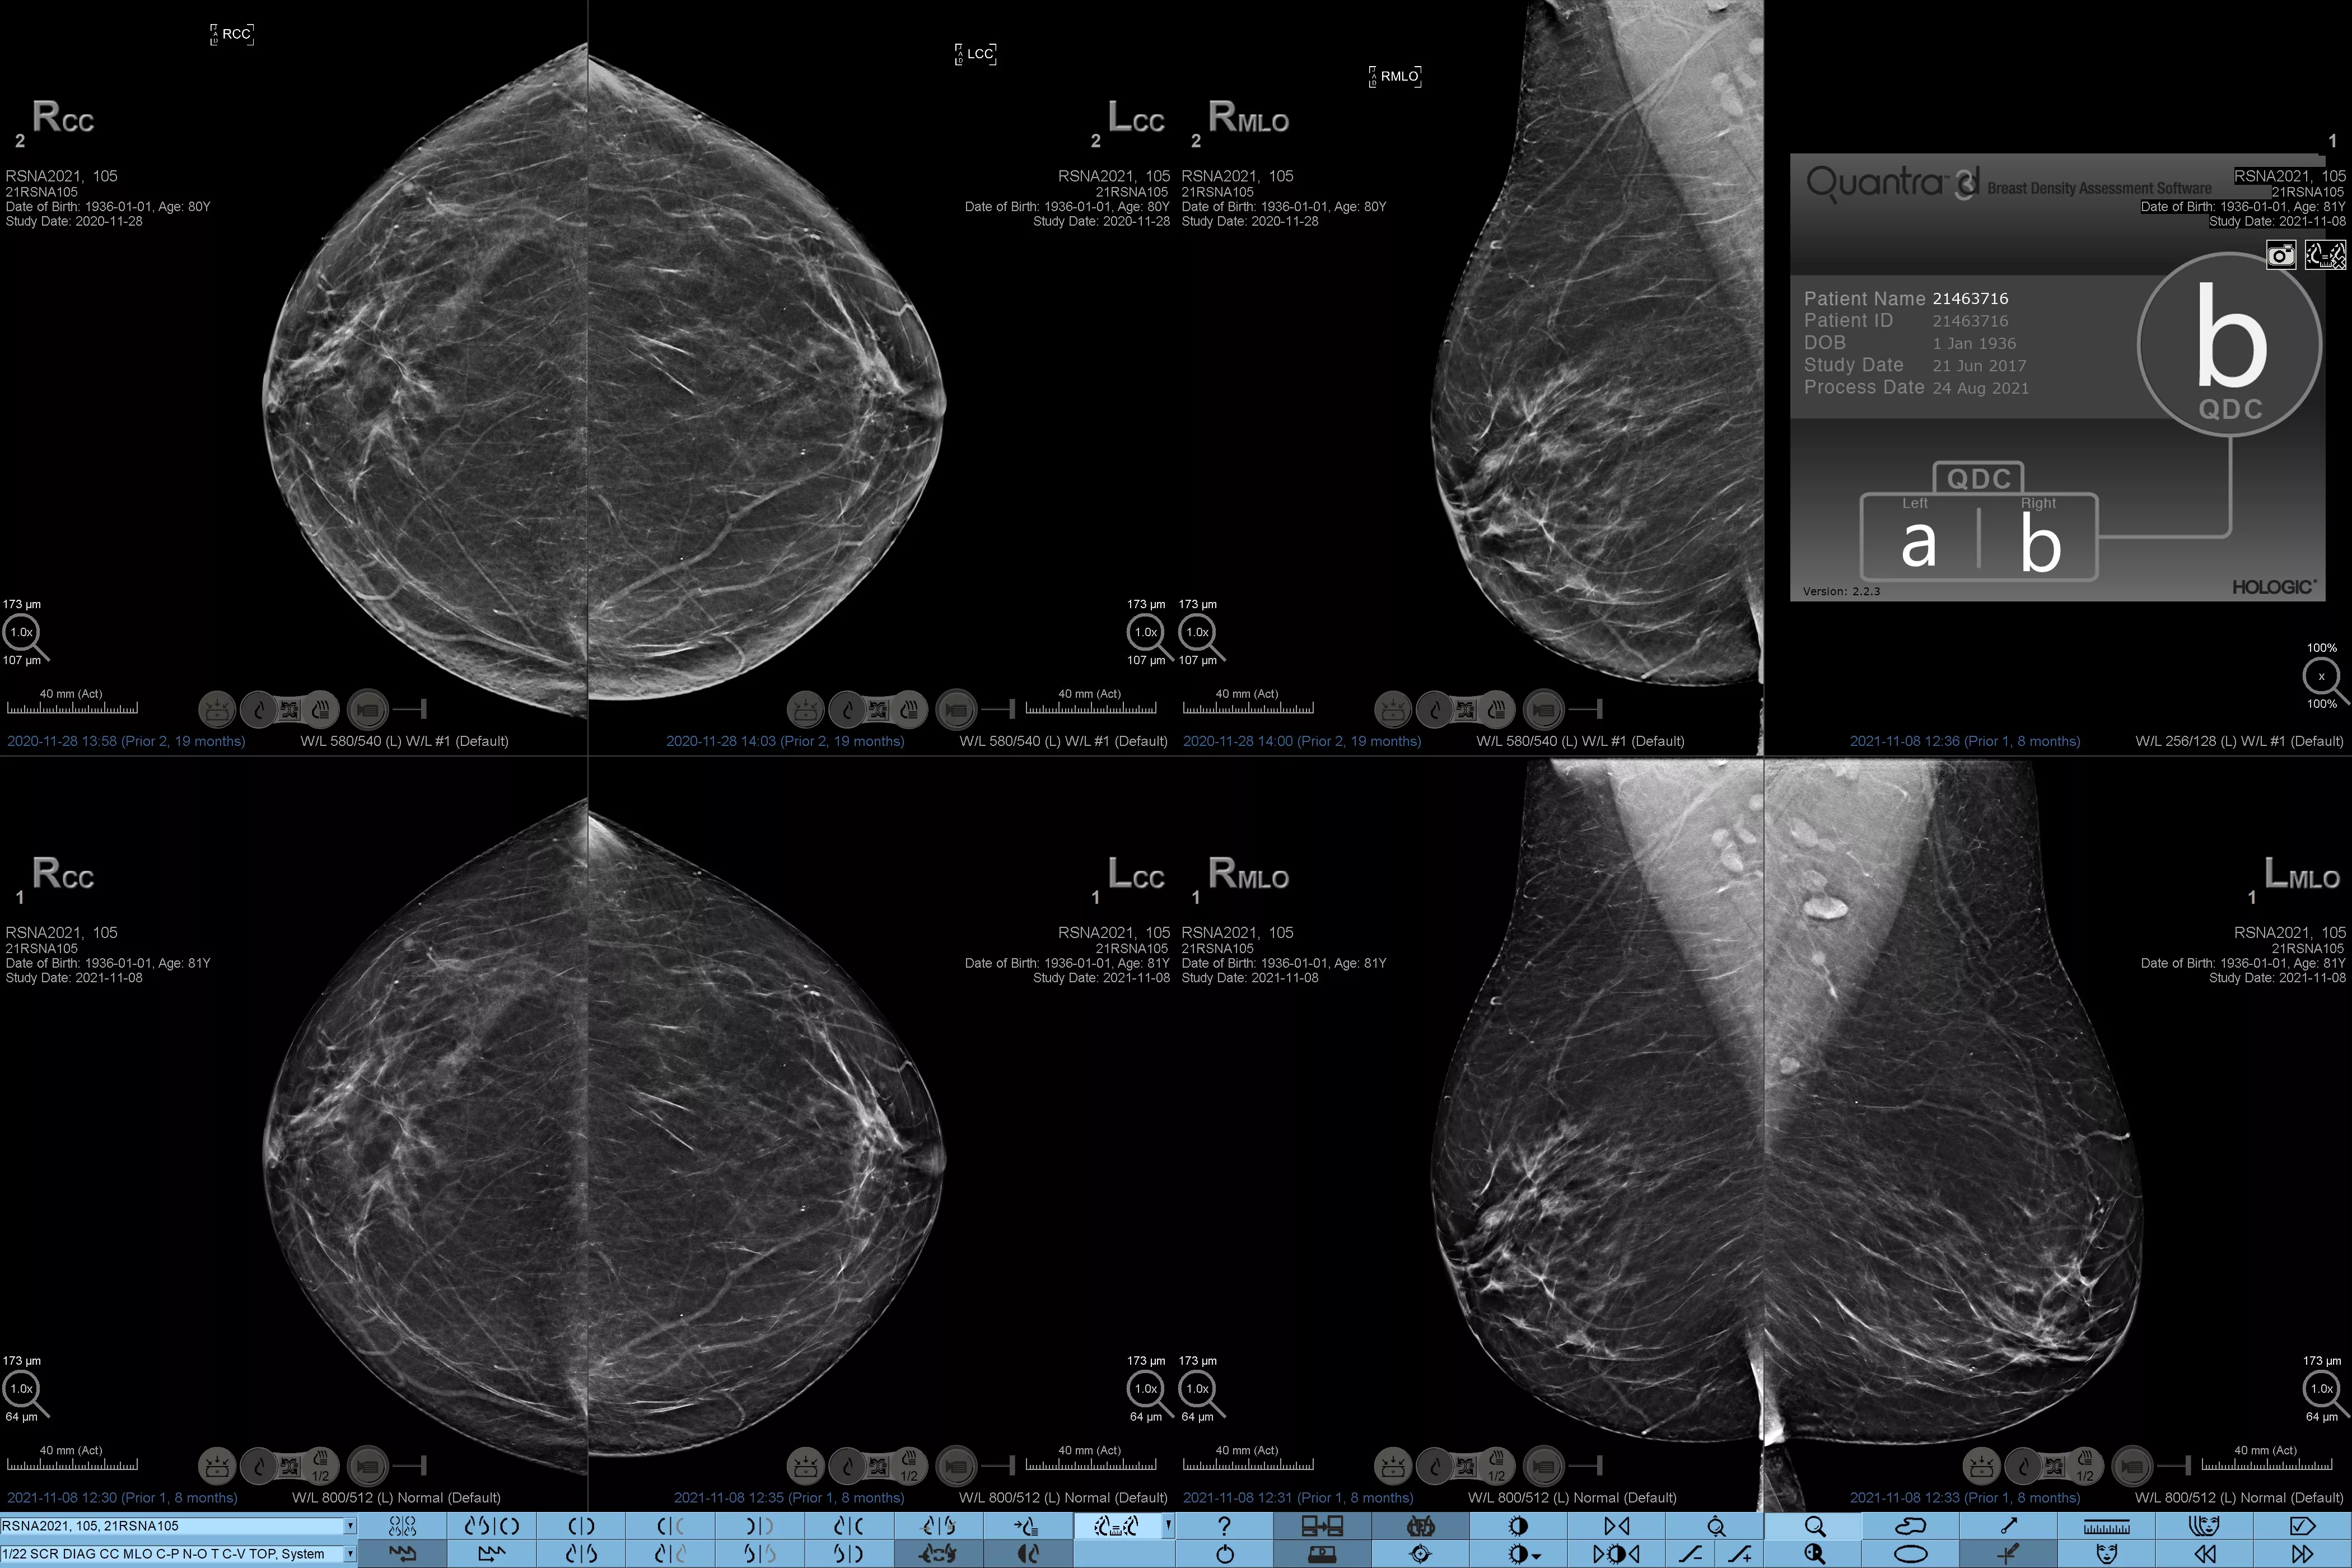

Eine höhere Brustdichte geht bekanntlich mit einem höheren Brustkrebsrisiko einher.1 Eine präzise, objektive Analyse ist daher entscheidend. Die durch maschinelles Lernen unterstützte Software der Quantra Technologie analysiert sowohl 2D™- als auch Tomosynthese-Bilder in Bezug auf Verteilung und Textur des Parenchymgewebes. Sie teilt die Brüste entsprechend der Leitlinie der 5. Auflage des BI-RADS Atlas des American College of Radiology (ACR) nach ihrer Zusammensetzung in vier Brustdichte-Kategorien ein.2

Objektiver Machine-Learning-Algorithmus, der die Brustdichte-Kategorie auf Basis der Analyse von Textur und Muster des Brustgewebes zuordnet.

Der objektive Algorithmus der Quantra-Software analysiert sowohl 2D- als auch Tomosynthese-Bilder und unterstützt Sie bei Ihrer Analyse durch:

• Unabhängigkeit von subjektiver visueller Beurteilung für eine konsistentere und zuverlässigere Einstufung.*

*Die Scores basieren auf den ACR BI-RADS-Kategorien nach den revidierten Leitlinien der 5. Auflage des vom American College of Radiology (ACR) herausgegebenen BI-RADS-Atlas. Dadurch werden Struktur und Textur im Vergleich zum Volumen bei der Dichtebestimmung berücksichtigt.